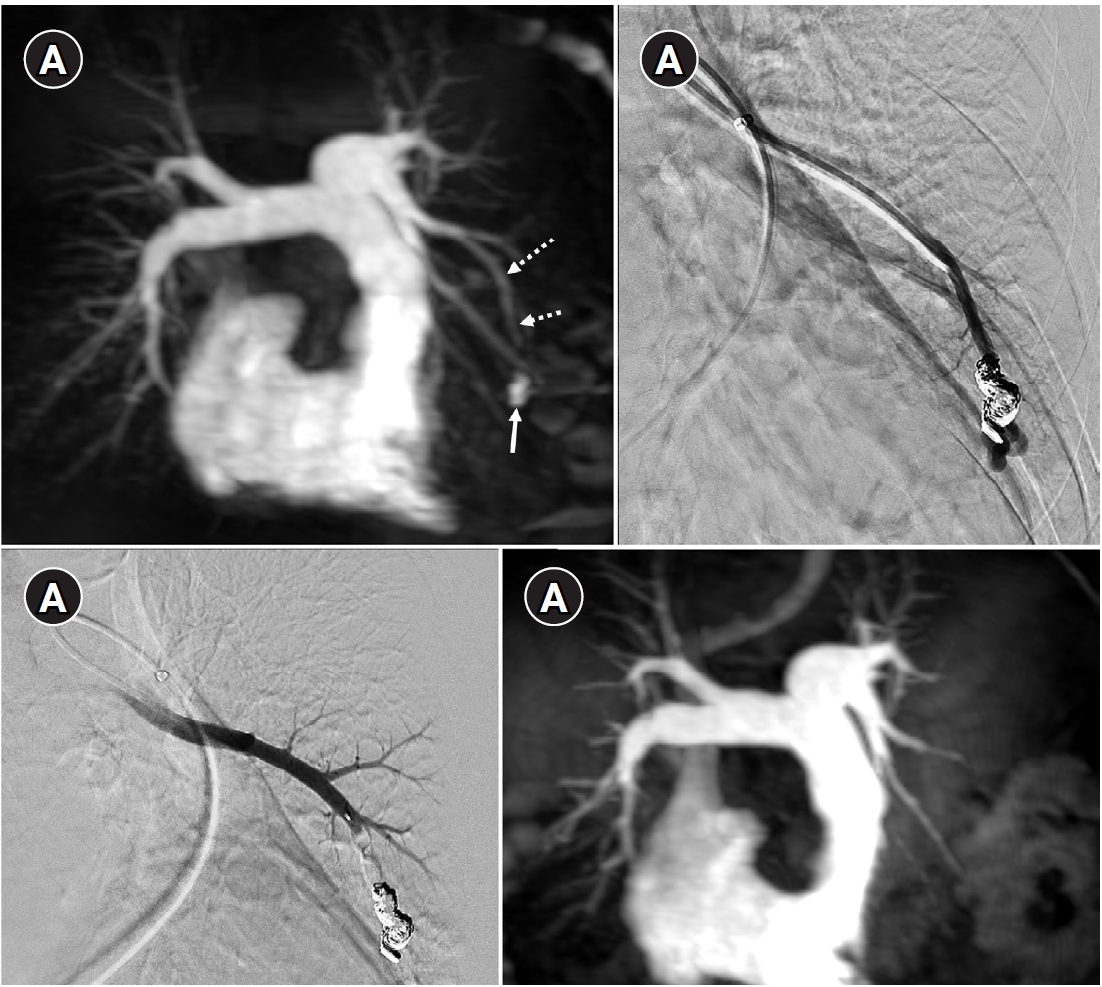

Fig. 5.

Embolization procedure in a patient with a feeding artery diameter of 2.6 mm and a venous sac diameter of 8 mm in the right lower lobe. (A) Selective angiography of the right lower lobe pulmonary arteriovenous malformation. (B) A 7 mm Amplatzer vascular plug type IV (arrow) was deployed into an approximately 8 mm venous sac, and it was determined that this would not provide adequate embolization effect. (C) By repositioning the Amplatzer plug and deploying it at the distal part of the feeding artery (arrow), it becomes clear that an Amplatzer vascular plug sufficiently larger than the feeding artery’s size is needed to effectively achieve embolization.

Historically, detachable balloons were used as an embolization material; however, they are no longer utilized in current practice [18]. In the context of PAVM embolization, the use of coils, vascular plugs, or a combination of both is now standard practice [19-21]. Since the development of detachable coils, they have offered advantages over pushable coils, particularly in terms of repositioning during the procedure. They can even be fully retrieved and redeployed if necessary, enhancing procedural safety and control. It is crucial to prioritize minimizing the recanalization rate while ensuring the overall safety of the procedure when selecting the appropriate embolic materials and techniques. Feeding artery coil embolization was historically regarded as the standard approach, whereas venous sac embolization was discouraged because of the perceived risk of rupture [22]. However, with the introduction of newer venous sac embolization techniques, recent findings now indicate that tightly packing the venous sac with coils can achieve a higher success rate than the traditional feeding artery approach (Fig. 2) [22-25]. Additionally, vascular plugs, including micro-vascular plugs (Medtronic, Minneapolis, MN, USA) and Amplatzer vascular plugs (Abbott Vascular, Saint Paul, MN, USA) have also demonstrated a higher success rate compared to feeding artery coil embolization (Fig. 4) [26-28]. In the case of vascular plugs, the risk of device migration is relatively low. Moreover, an additional advantage is that the device can be repositioned if the sizing is not ideal or if it is not deployed in the exact desired location. This flexibility enhances the precision of the procedure (Fig. 5). In a recent European guideline, there is also a recommendation to consider vascular plug embolization as a first-line option whenever possible, rather than coil embolization [11]. Additionally, a recent meta-analysis recommended vascular plugs or venous sac coil embolization, noting that vascular plugs had a recanalization rate of 13.6% compared to 32.7% for coil-only embolization. Similarly, venous sac embolization showed a 3.8% recanalization rate, while feeding artery embolization had a rate of 24.3%. Additionally, a recent meta-analysis has recommended the use of vascular plug or venous sac coil embolization, as these techniques have demonstrated a lower persistence rate compared to other methods [21]. This shift is largely in response to the relatively high recanalization rate associated with feeding coil embolization. In the case of embolization using vascular plugs, the plug should be deployed at the most distal segment of the feeding artery just before the venous sac in order to preserve the normal pulmonary artery. Since the pulmonary artery contains less elastin and has a thinner wall compared to systemic arteries, it is more distensible [29]. Therefore, in the author's experience, oversizing by about 50% to 100% has been effective in reducing the recanalization rate. When performing venous sac coil embolization, it is important to use coils large enough to create a stable framing coil larger than the draining vein diameter, thereby preventing coil migration. After establishing this frame, the venous sac and the proximal feeding artery should be carefully packed to achieve complete occlusion.

Fig. 5. Embolization procedure in a patient with a feeding artery diameter of 2.6 mm and a venous sac diameter of 8 mm in the right lower lobe. (A) Selective angiography of the right lower lobe pulmonary arteriovenous malformation. (B) A 7 mm Amplatzer vascular plug type IV (arrow) was deployed into an approximately 8 mm venous sac, and it was determined that this would not provide adequate embolization effect. (C) By repositioning the Amplatzer plug and deploying it at the distal part of the feeding artery (arrow), it becomes clear that an Amplatzer vascular plug sufficiently larger than the feeding artery’s size is needed to effectively achieve embolization.